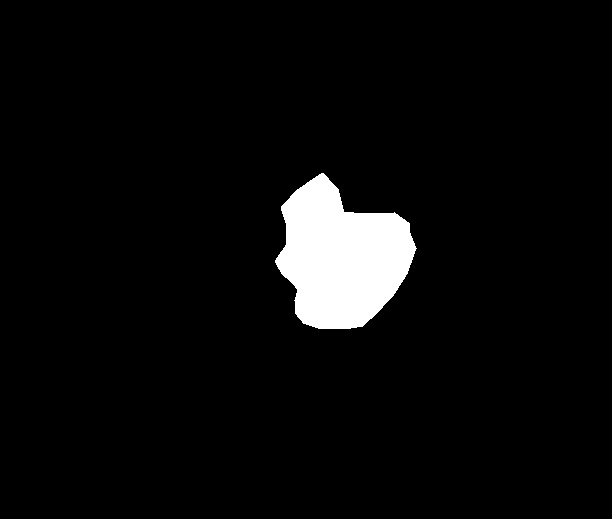

A few sample images and the corresponding masks of the polyp dataset in HyperKvasir are shown in Fig 2. The polyp images are RGB images. The masks of the polyp images are single-channel images with white () for true pixels, which represent polyp regions, and black () for false pixels, which represent clean colon or background regions. In this dataset, there are different sizes of polyps. The distribution of polyp sizes as a percentage of the full image size is presented in the histogram plot in Fig 3, and we can observe that there are more relatively small polyps compared to larger polyps. Additionally, a subset of this dataset was used to prove that the performance of segmentation models trained with small datasets can be improved using our SinGAN-Seg pipeline, and the whole dataset was used to show the effect of using SinGAN-Seg generated synthetic images instead of a large dataset which has enough data to train segmentation models. In this regard, this dataset was used for two purposes:

To understand the difference between the mask distribution of real images and synthetic images, we plotted pixel distribution of masks of synthetic images in Fig 6. This plot is comparable to the pixel distribution presented in Fig 3. The randomness of the generations made differences in the distribution of true pixel percentages compared to the true pixel distribution of real masks of real images. However, the overall shape of synthetic data mask distribution shows a more or less similar distribution pattern to the real true pixel percentage distribution.